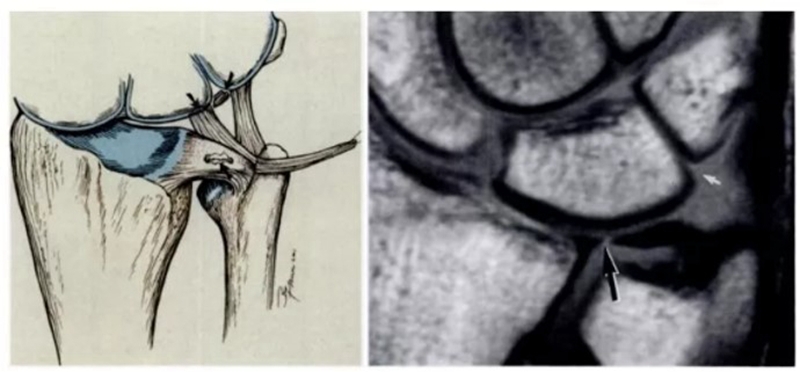

半月板同系物是关节盘远侧增厚的尺侧副韧带纤维形成半月板类似体,与关节盘共同起于尺骨背侧靠近尺骨的边缘,有尸解证实其附着于豌豆骨。

半月板同系物